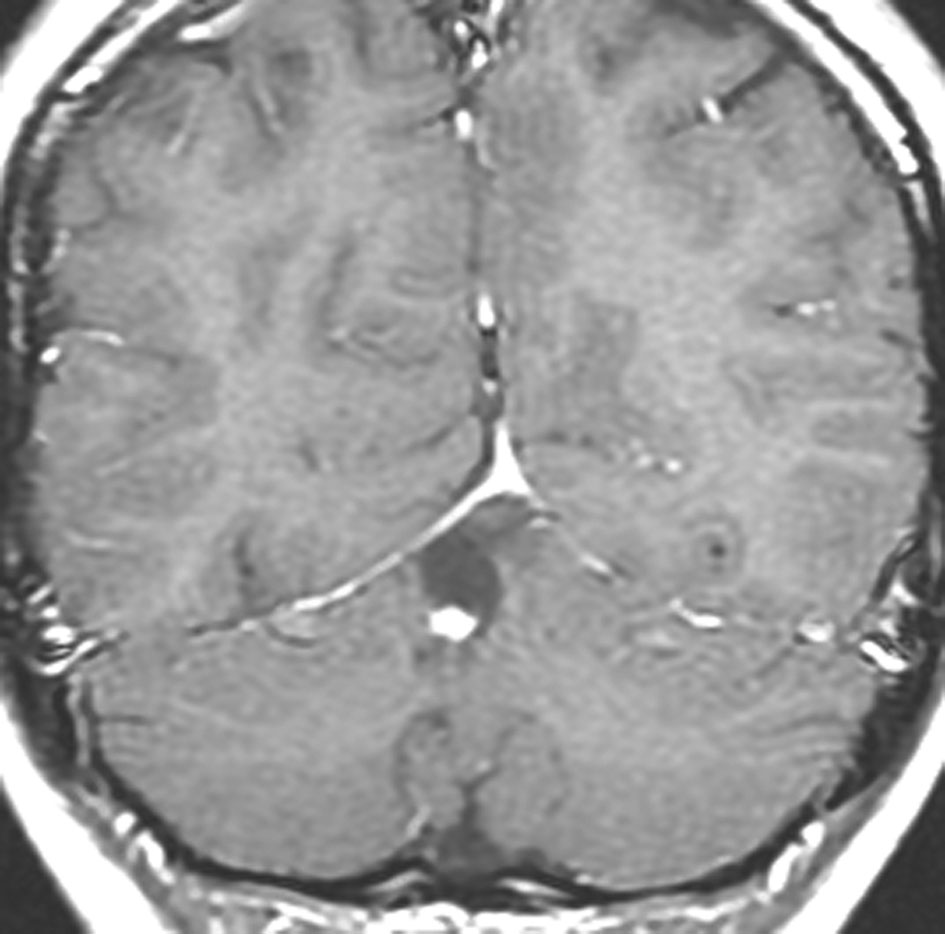

18歳で発症して,60歳まで無治療の大きな視床下部毛様細胞性星細胞腫

hypothalamic pilocytic astrocytoma

1968年 18歳の時に頭痛嘔吐で発症しました。第3脳室腫瘍と閉塞性水頭症の診断だけで,シャント手術を受けました。手術も化学療法も放射線治療もされていません。下の画像は60代で撮影されたものです。この例では,第3脳室内に増大した大きな毛様細胞性星細胞腫が,視床下部下垂体障害を出すことなく,自然経過で増大停止 growth arrest して,カチカチに固まってしまうということを教えてくれます。でも,こんなに都合よく経過観察できる例も珍しいです。

CTでは強い石灰化があります。右のT2強調画像では腫瘍は等信号,視交叉の後ろにあります。内部の低信号は石灰化です。

T1強調画像では等信号,ガドリニウム増強でごく一部がまだらに増強されます。